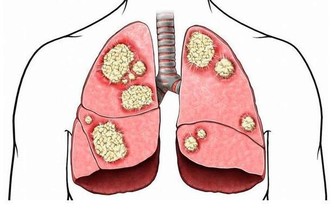

充足的膳食纖維能夠促進腸道蠕動和吸水膨脹,防止便秘,縮短有害物質在腸道的停留時間,有助於預防和降低腸癌發生率。